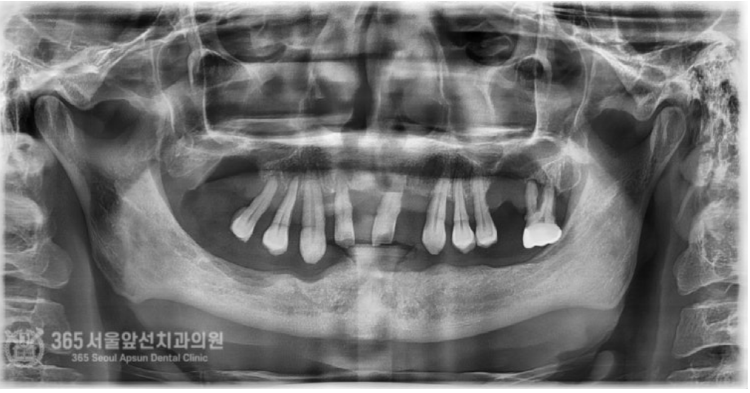

안녕하세요. 주안동치과 365서울앞선치과의원입니다. 오늘 소개할 증례의 환자분은 위아래 턱뼈가 극단적으로 없었던 환자분입니다. 근처 치과를 돌고 돌다 도저히 치료가 불가능하다고 판정 받았는데 지인분의 소개로 저희 주안동치과에 내원하게 되었던 분입니다. 환자분께서는 치료가 가능할지 걱정이 많으셨는데, 간단하게 답변드렸습니다. 뼈가 없으면 만들면 되고, 신경이 있으면 피하면 됩니다. 걱정은 저희가 할테니 환자분께서는 걱정하실 필요없겠습니다 ㅎㅎ 촬영일시 : 2024.07.03. 처음 내원하셨던 당시 파노라마 엑스레이 사진입니다. 위턱의 치아들이 전체적으로 흔들리고 당장 손가락으로 뽑아도 뽑힐 지경의 상황입니다. 또한 양쪽 상악동 부위의 잔존골이 거의 없으며, 상악동 천공 양상도 관찰됩니다. 아래턱의 경우는 더욱 심각합니다. 일단 과도한 골흡수로 어금니 부위에는 임플란트 식립 자체가 불가능할 정도의 뼈 상태입니다. 위턱의 치아들을 발치하고 뼈를 만들어 주면서 상악동 거상술을 동반하여 동시에 임플란트를 심어드렸습니다. 아래턱의 경우는 신경관이 위치하고 있기 때문에 신경관의 위치를 파악하여 정교하게 신경을 피해서 임플란트를 식립하였습니다. 위쪽, 아래쪽 모두 수술 난이도는 최상에 속한다고 보시면 되겠습니다. 촬영일시 : 2024.10.03. 수술이 완료되고 체크 과정에서 찍은 파노라마 엑스레이 사진입니다. 반듯하게 정확한 위치에 임플란트들이 위치되었습니다. 이렇게 반듯하게 식립된 임플란트를 보면 기분이 편안해집니다 ㅎㅎ 경험이 있는 의사라면 네비게이션 수술 혹은 수술용 가이드의 도움 없이 눈으로 보고 심더라도 가이드 보다 더 정확하게 수술이 가능합니다 ㅎㅎ 촬영일시 : 2024.12.02. 수술 후 체크 과정에서 잇몸의 상태입니다. 깨끗하게 낫고 있습니다ㅎㅎ 보철물의 제작은 디지털 방식을 통해 진행됩니다. 디지털 방식을 통해서 정밀한 보철물 디자인이 가능합니다.